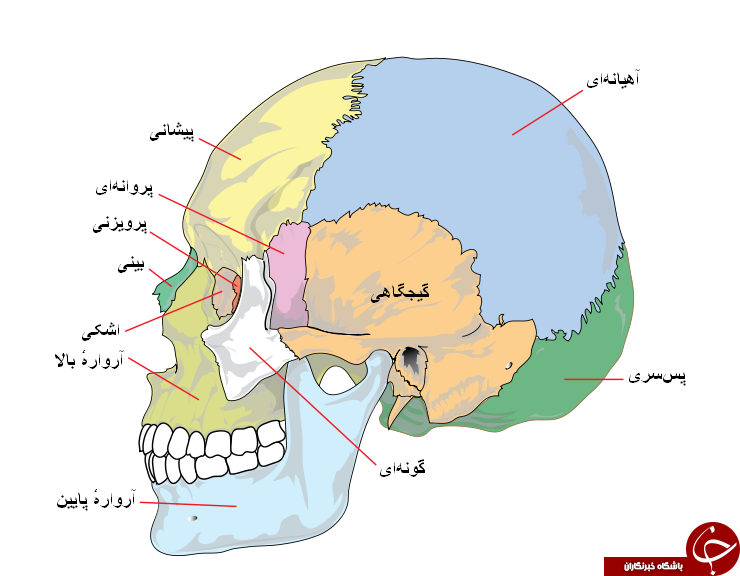

عکس اسکلت بدن انسان

عکس اسکلت بدن انسان. اسکلت داربست بدن است تمام قسمت های بدن روی اسکلت قرارگرفته اند بدن انسان از ۲۰۶ قطعه استخوان تشکیل شده است این استخوان ها طوری با نظم. هر قسمت بدن از انواع مختلف سلول تشکیل شده است. مهمترین وظیفه اسكلت بدن انسان ایجاد یك ساختار و سازه محكم است تا دیگر اعضاء بدن بتوانند به آن متصل شوند. سازه و چهارچوب اصلی بدن.

اسکلت داربست بدن است تمام قسمت های بدن روی اسکلت قرارگرفته اند بدن انسان از ۲۰۶ قطعه استخوان تشکیل شده است این استخوان ها طوری با نظم کنار هم قرار گرفته اند که انسان را قادر می سازد حرکات دقیقی داشته باشد. بدون اسكلت بدن مانند كرم شل و نرم است و این نوع شكل بندی نمیتواند. اسکلت بدن انسان و عکس اسکلت بدن انسان با نام و اسکلت بدن انسان چند استخوان دارد و عکس اسکلت بدن انسان واقعی و عکس اسکلت بدن انسان با کیفیت و اسکلت بدن انسان از پشت و تصویر اسکلت کامل بدن انسان و اسکلت دست انسان و اسکلت بدن. معرفی بدن انسان اسکلیت.

اسکلت داربست بدن است تمام قسمت های بدن روی اسکلت قرارگرفته اند بدن انسان از 206 قطعه استخوان تشکیل شده است این استخوان ها طوری با نظم کنار هم قرار گرفته اند که انسان را قادر می سازد حرکات دقیقی داشته باشد. اسكلت به بدن شكل میدهد. عکس اسکلت بدن انسان زن و مرد آناتومی ساتین 16 سپتامبر 2017.